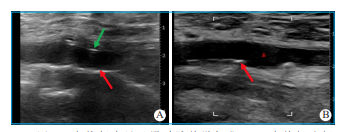

超声引导穿刺步骤与技巧:①穿刺前,用水湿润皮肤,使探头与皮肤之间没有气体,保证超声视野的清晰性。②若在局部麻醉下穿刺,穿刺前不宜注射过多的利多卡因,以防止影响穿刺视野,可穿刺成功后补充利多卡因。③深压和轻抬超声探头以便识别股动脉和股静脉,股静脉往往会被完全压瘪,而动脉往往不会完全压瘪,并且动脉具有搏动性;也可采用彩色血流显示和区分动静脉。④选择目标血管时,超声探头正切血管,注意右腿和左腿穿刺时探头角度有所不同,左右滑动超声探头,将目标血管呈现在超声显示屏正中,沿着血管的长轴缓慢移动,明确股总动脉分叉(图2),确保看到股浅动脉和股深动脉汇合成股总动脉的过程,并避开血管壁钙化和狭窄(图3),选择合适的动脉穿刺点。⑤穿刺时,穿刺针从探头正中间进针,并且进针距离探头一般为3~5mm,根据患者胖瘦程度适当调整,可轻轻上下推送穿刺针使血管上方组织随之移动,观察进针方向是否位于动脉的正上方(图2D)。⑥置入临时起搏器需要建立静脉穿刺入路。股静脉往往位于股动脉的内侧和下方,因此股静脉穿刺时,要在探头的偏内侧进针,可以顺着静脉长轴方向移动,找到静脉与动脉内外分开最宽的位置,进针后保持一定负压回抽趋势。

图3 血管超声显示股动脉管壁钙化  A.血管探头探及股动脉前壁(绿色箭头)和后壁均存在长轴延续性钙化(红色箭头);B.血管探头探及股动脉仅后壁存在局限性钙化(红色箭头)。